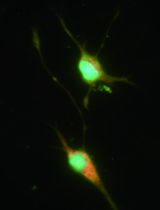

The cardiac conduction system allows the synchronized propagation of electrical activity through heart muscle. This is initiated by the spontaneous activity of the specialized pacemaker cells of the sino-atrial node (SAN). The SAN region underlies automaticity in mammals and therefore has a crucial role in the pathogenesis of cardiac disorders such as arrhythmia. Isolation of SAN tissue and SAN cells is critical to advance our understanding of SAN structure and function in health and disease. Initially, isolation of SAN tissue and SAN cells was carried out in the rabbit owing to its larger size and similar electrical properties to human. This protocol was optimized by Mangoni and Nargeot (2001) for use in mice to take advantage of advancements in transgenic models. Here, we provide a step-by-step guide to dissecting the SAN tissue and isolating pacemaker cardiomyocytes from mouse hearts using an enzyme digestion approach.

Cardiovascular diseases and abnormalities are a major cause of morbidity and mortality and are major burden on healthcare systems. Arrhythmias as result of changes in the structure, rate and rhythm of the cardiac conduction system underlie many cardiac disorders. In the past, a lack of availability of homogenous conduction system cell lines has proven to be a hindrance to investigators wishing to study the function of conduction system cells in health and disease. The emergence of transgenic animal models of cardiac abnormalities provides an even greater impetus to reliably isolate healthy conduction system cells. Intact nodes allow investigations into expression profiles of important signaling proteins and genes using immunohistochemistry and qPCR approaches. More detailed functional analysis is possible on isolated single nodal cells using patch-clamp for example. The SAN tissue and the cells it consists of were first isolated many decades ago (Noble and Tsien, 1968). However, the cell population isolated was generally a mixed population. SAN specific cells were first isolated from rabbit SAN by DiFranscesco et al. (1986) in the mid-1980s to allow study of ion channel expression. More recently, the protocol was adapted for isolation of SAN cells from mice by Mangoni and Nargeot (2001). This has allowed transgenic mouse models specific to the SAN to be studied in greater detail. We describe the procedure for isolating the SAN tissue and single SAN cells. The intact node can be used for investigation of gene and protein expression as well as for tissue histology, whilst acutely isolated cells can be interrogated in detail for their electrophysiological properties.